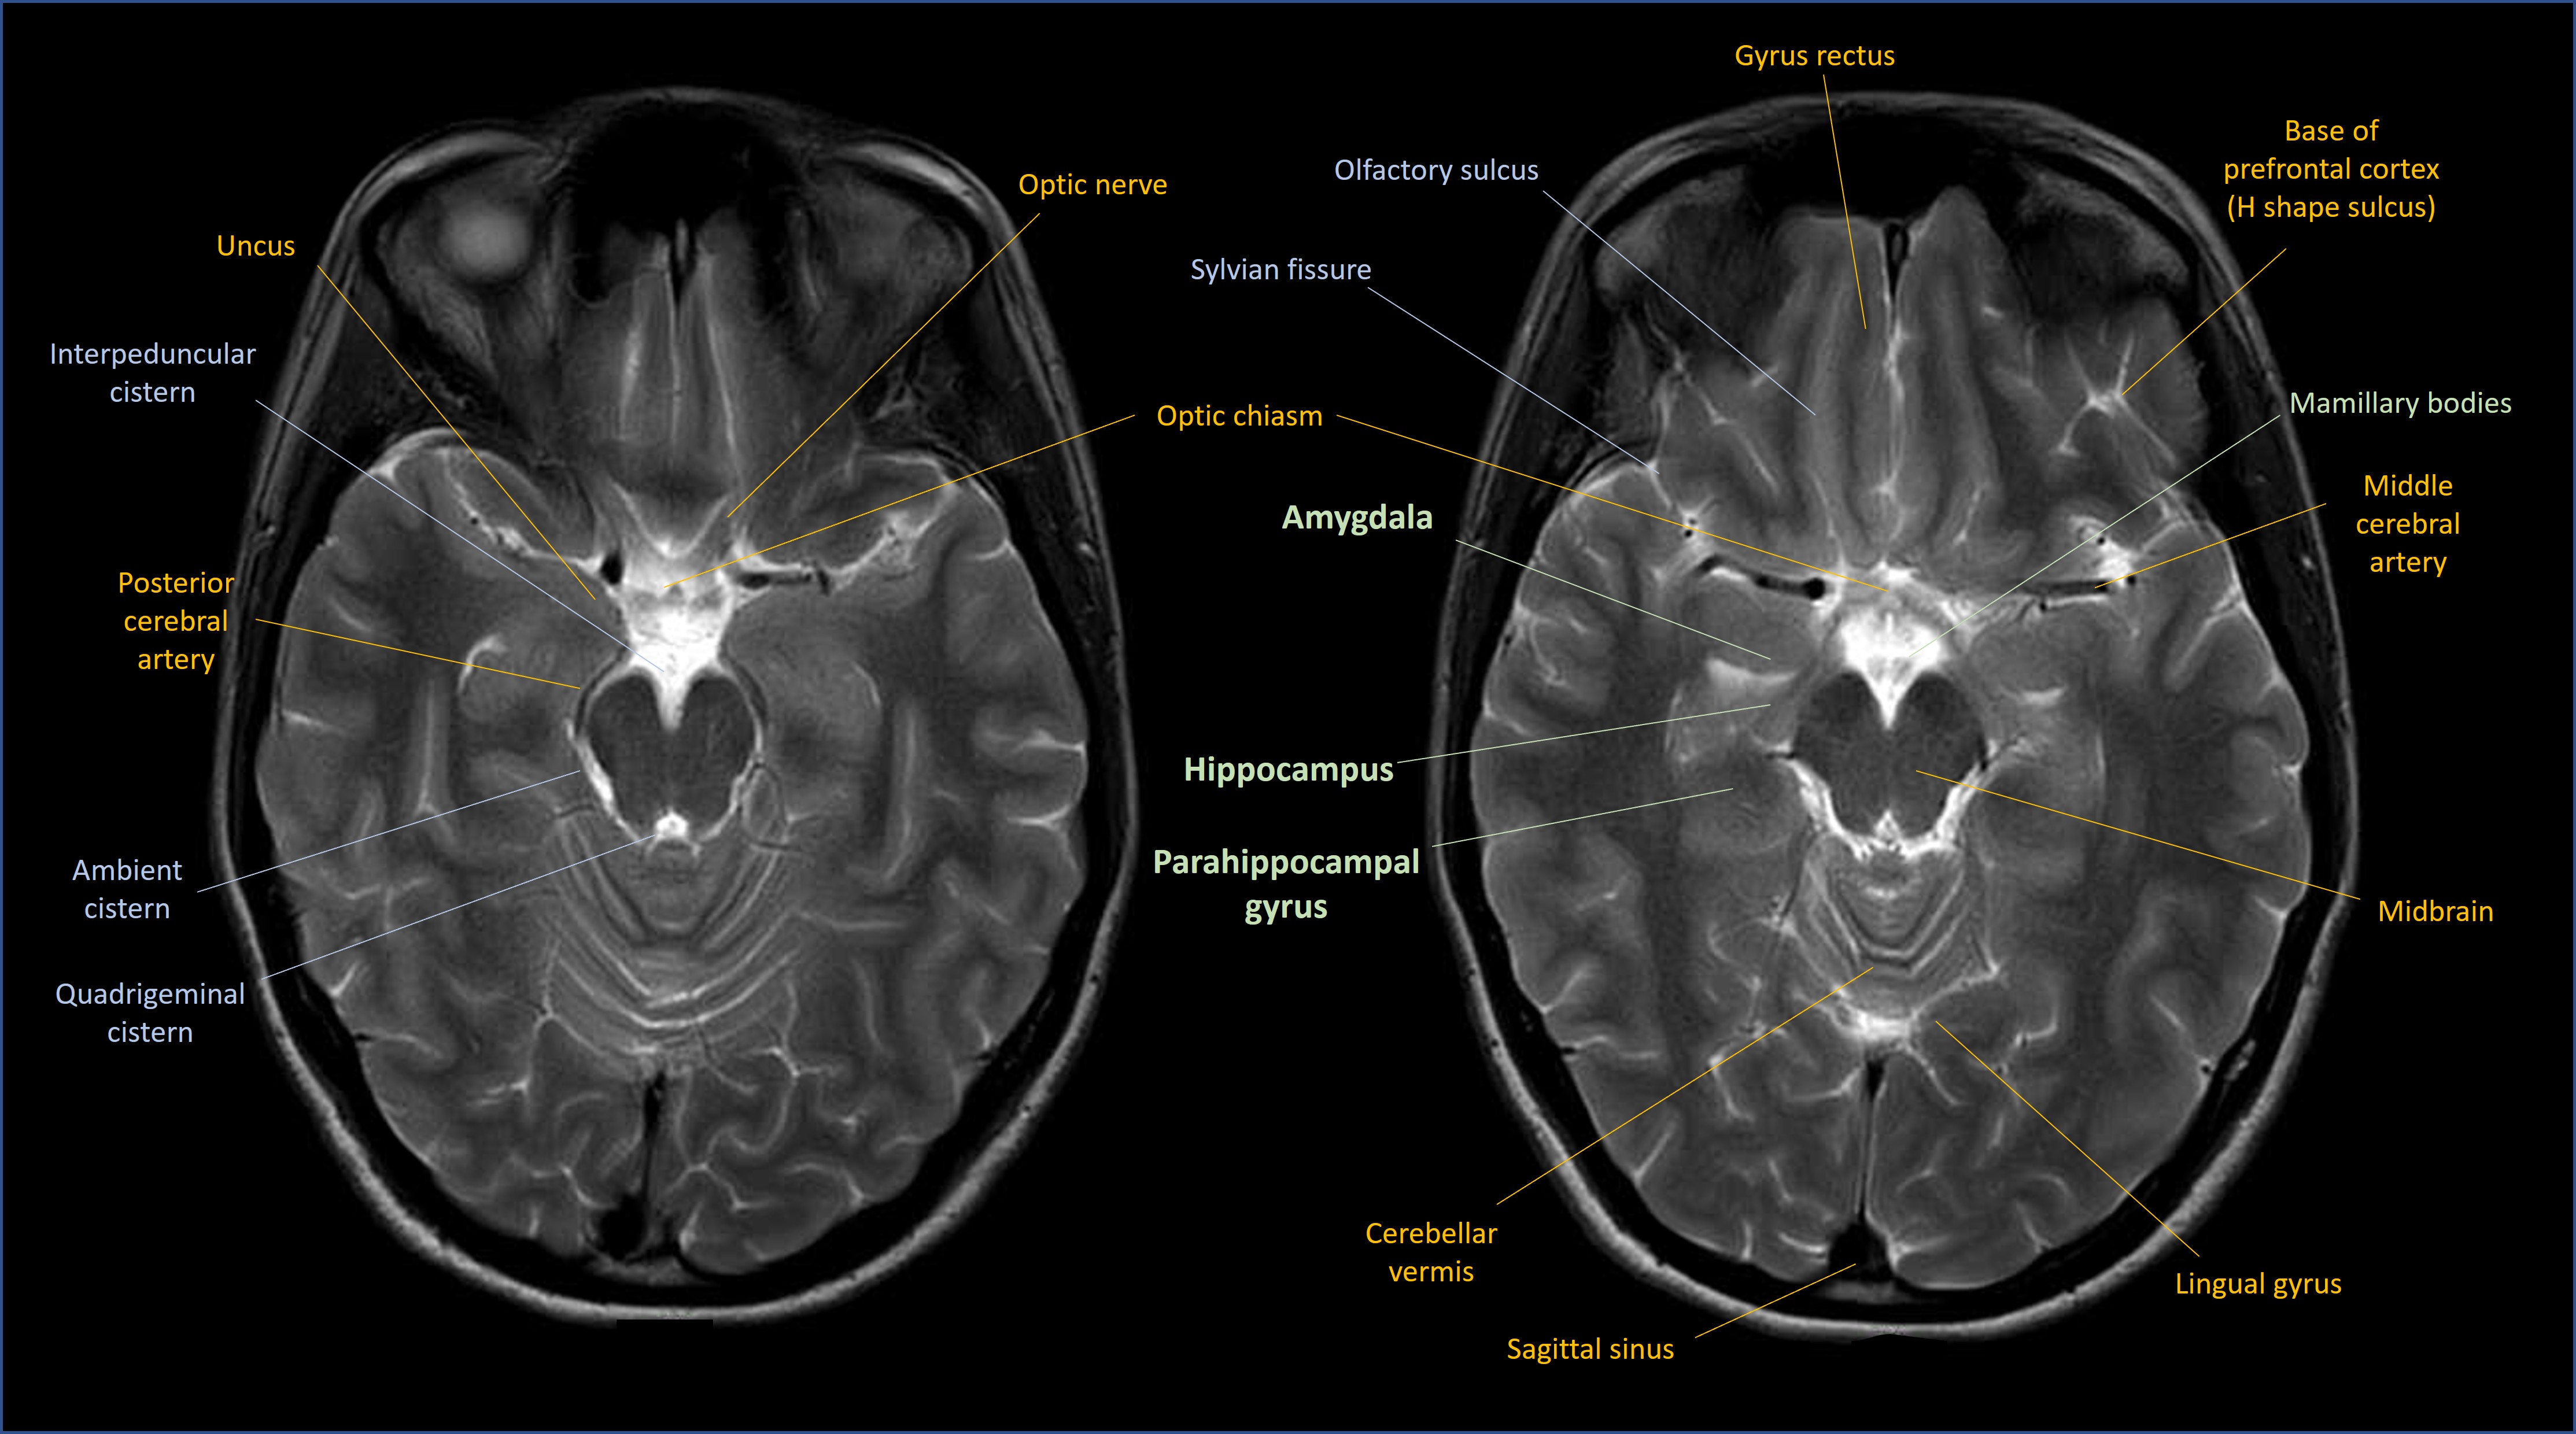

The most famous part of this circuit is the hippocampus - a seahorse-shaped area of cortex. We have two, one in each of the mesial temporal lobes on either side. Note that for the temporal lobe the term ‘mesial’ is generally used rather than ‘medial’. The following scans show the key anatomy in coronal, sagittal and axial views respectively.

The hippocampus is where the Papez circuit starts. The hippocampus is involved in multiple diseases that cause memory problems - the most famous being Alzheimer's, in which pathology affects it early on - and hippocampal atrophy is visible on MRI even at an early stage.

The anterior thalamus sends fibres out to the cingulate gyrus, above the corpus callosum. The cingulate then returns signal down to the temporal lobes in the parahippocampal gyrus (the entorhinal cortex), and from there it loops back to the hippocampus.

The amygdala is an important component, and the cingulate also has a role in how we process emotions. Cingulate lesions can sometimes render a patient indifferent, with no reaction or motivation arising as a result of experiences. This is also induced surgically to treat intractable pain (cingulotomy) - the pain doesn't cease, but the emotional reaction to it is blunted. So limbic damage can produce 'negative' deficits from loss of function.

At the opposite end, ‘positive’ limbic system symptoms include the fear and anxiety that can be experienced in seizures involving the amygdala or cingulate gyrus - the system expressing itself abnormally.